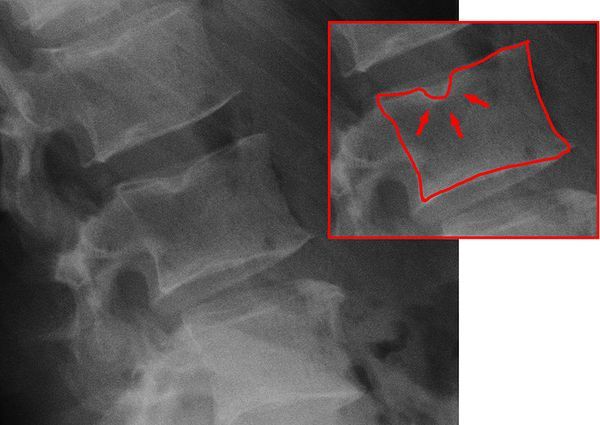

В основе патологического кифоза лежит дисбаланс между передними и задними структурами позвоночника. Например, при болезни Шейермана — Мау нарушается процесс окостенения замыкательных пластинок, покрывающих концы позвонков, из-за чего передние отделы позвонков растут медленнее, приобретая клиновидную форму [4]. При этом в зонах роста возникают грыжи Шморля: пульпозное ядро диска внедряется в тело позвонка, что усугубляет деформацию. Часто они появляются в период быстрого роста скелета, если пациент занимается тяжёлым физическим трудом.

![Грыжа Шморля [15] Грыжа Шморля [15]](/media/bolezny/patologicheskiy-kifoz/gryzha-shmorlya-15_s.jpeg?dummy=1760604053935)

Грыжа Шморля [15]